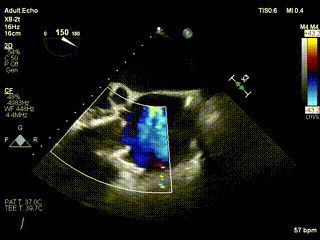

2021年12月24日,復旦大學附屬中山醫院葛均波院士團隊成功應用LuX-Valve Plus為一例極重度三尖瓣反流(TR)合并房顫、房缺的患者完成了經血管三尖瓣置換術,這是在前基礎上,本周完成的第三例經血管三尖瓣置換手術,葛均波院士、周達新教授等與心外科魏來教授、賴顥教授,心超室的潘翠珍教授、李偉教授及麻醉科的郭克芳教授共同完成了本周手術,均獲得圓滿成功!患者術后超聲顯示無TR,臨床癥狀明顯改善。本周手術的成功也為LuX-Valve Plus救治性臨床研究添上了濃墨重彩的一筆。

三例患者入院后,葛均波院士團隊周達新教授、潘文志教授、張源博士、陳莎莎博士及心超室的潘翠珍教授、李偉教授對患者的情況進行詳細評估和討論,最終決定為三例患者選擇LuX-Valve Plus40mm、50mm和50mm型號的瓣膜進行手術治療。手術后即刻拔除氣管插管,術后患者三尖瓣反流癥狀得到顯著改善,復查心超結果顯示人工三尖瓣瓣膜支架固定穩定,瓣葉關閉形態未見異常,未見明顯反流。